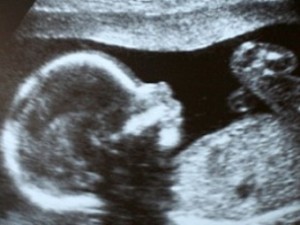

обязательного прослушивания сердцебиения будущего ребенка,

вернувшего здоровый материнский инстинкт большинству

латышек.